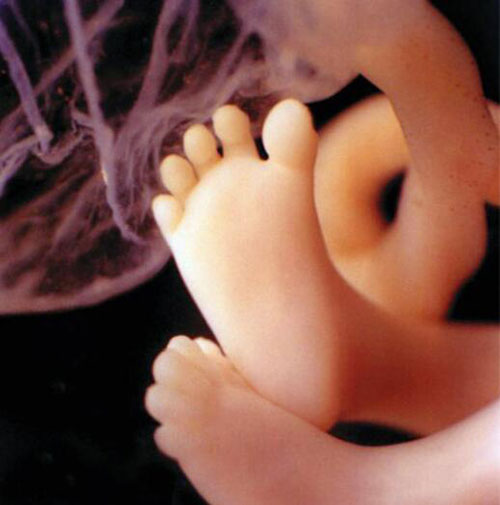

Hình chụp bàn chân đã phát triển đầy đủ các ngón của một thai nhi trong bụng mẹ.

Ảnh siêu âm bàn chân một thai nhi.